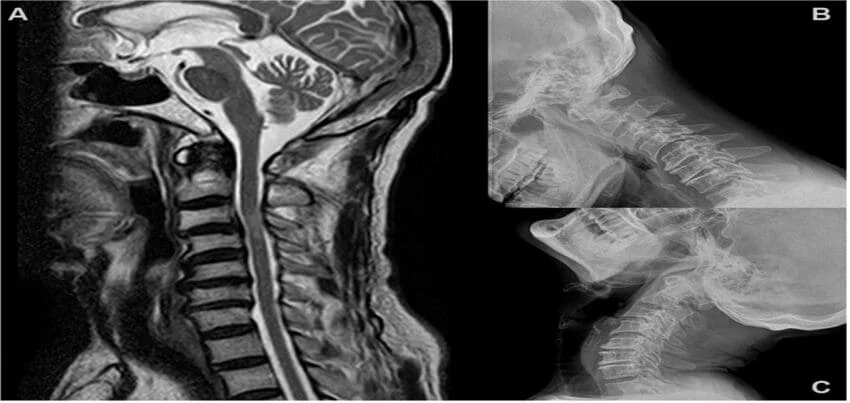

Magnetic Resonance Imaging (MRI) is a non-invasive diagnostic tool used to create detailed images of internal organs, tissues, and structures of the body. MRI Cervical Spine is a specialized imaging procedure used to evaluate the soft tissues of the neck, including the cervical vertebrae, intervertebral discs, and spinal cord.

The results of an MRI Cervical Spine can provide detailed information about the structures and tissues of the cervical spine, including any abnormalities or injuries. The images can be used to diagnose a range of conditions, such as herniated discs, spinal stenosis, or tumors, and can help guide treatment decisions.

Magnetic Resonance Imaging (MRI) of the cervical spine is a specialised imaging test that provides detailed pictures of the structures in the neck region, including the vertebrae, spinal cord, intervertebral discs, and surrounding soft tissues. This non-invasive procedure helps diagnose and monitor various conditions affecting the cervical spine.

Anatomy of the Cervical Spine

The cervical spine consists of seven vertebrae (C1 to C7) that support the skull and protect the spinal cord. Key structures include:

Types of MRI Sequences Used for the Cervical Spine

Different MRI sequences highlight various tissues and abnormalities:

1. T1-Weighted Imaging:

o Good for anatomical details.

o Fat appears bright, and fluid appears dark.

2. T2-Weighted Imaging:

o Excellent for identifying fluid and inflammation.

o Fluid and pathology (like a herniated disc) appear bright.

Interpretation of MRI Results

The MRI results are analyzed by a radiologist, who will provide a detailed report highlighting any abnormalities, including: